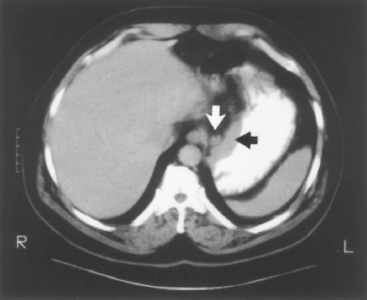

Figure 47-6. Computed tomography scan demonstrating mass along lesser curvature of the stomach (black arrow) and associated lymph node enlargement (white arrow).

Computed tomography (CT) can provide information both about the primary tumor and visceral metastatic disease. Because it is noninvasive and widely available, it is often the first staging modality that is employed in a patient diagnosed with gastric cancer. Patients who are found to have metastatic disease can be spared further, potentially invasive staging studies. When performed with intraluminal and intravenous contrast, CT can demonstrate infiltration of the gastric wall by tumor, gastric ulceration, and the presence of hepatic metastases (Figs. 47-6 and 47-7). CT may overestimate depth of invasion, but serosal involvement can be reliably assessed (sensitivity 83% to 100%, specificity 80% to 97%).34 The technique is less reliable for detection of small peritoneal metastases, which may be missed in 30% of cases.35 Similarly, evaluation of nodal disease by CT is limited, with accuracy of 70% to 80% even with modern CT techniques.36